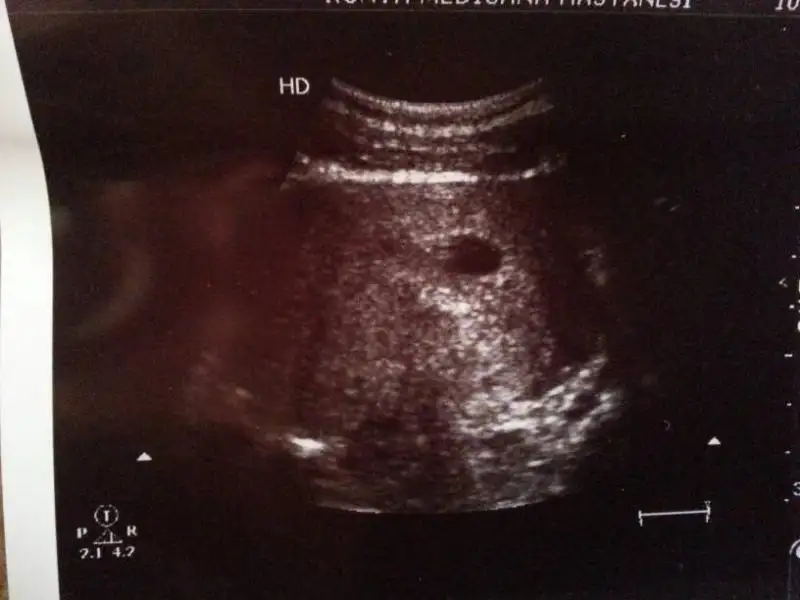

benim kız diyorr ama ben inanmıyorumm benim içime hep oğlan doğuyorrr